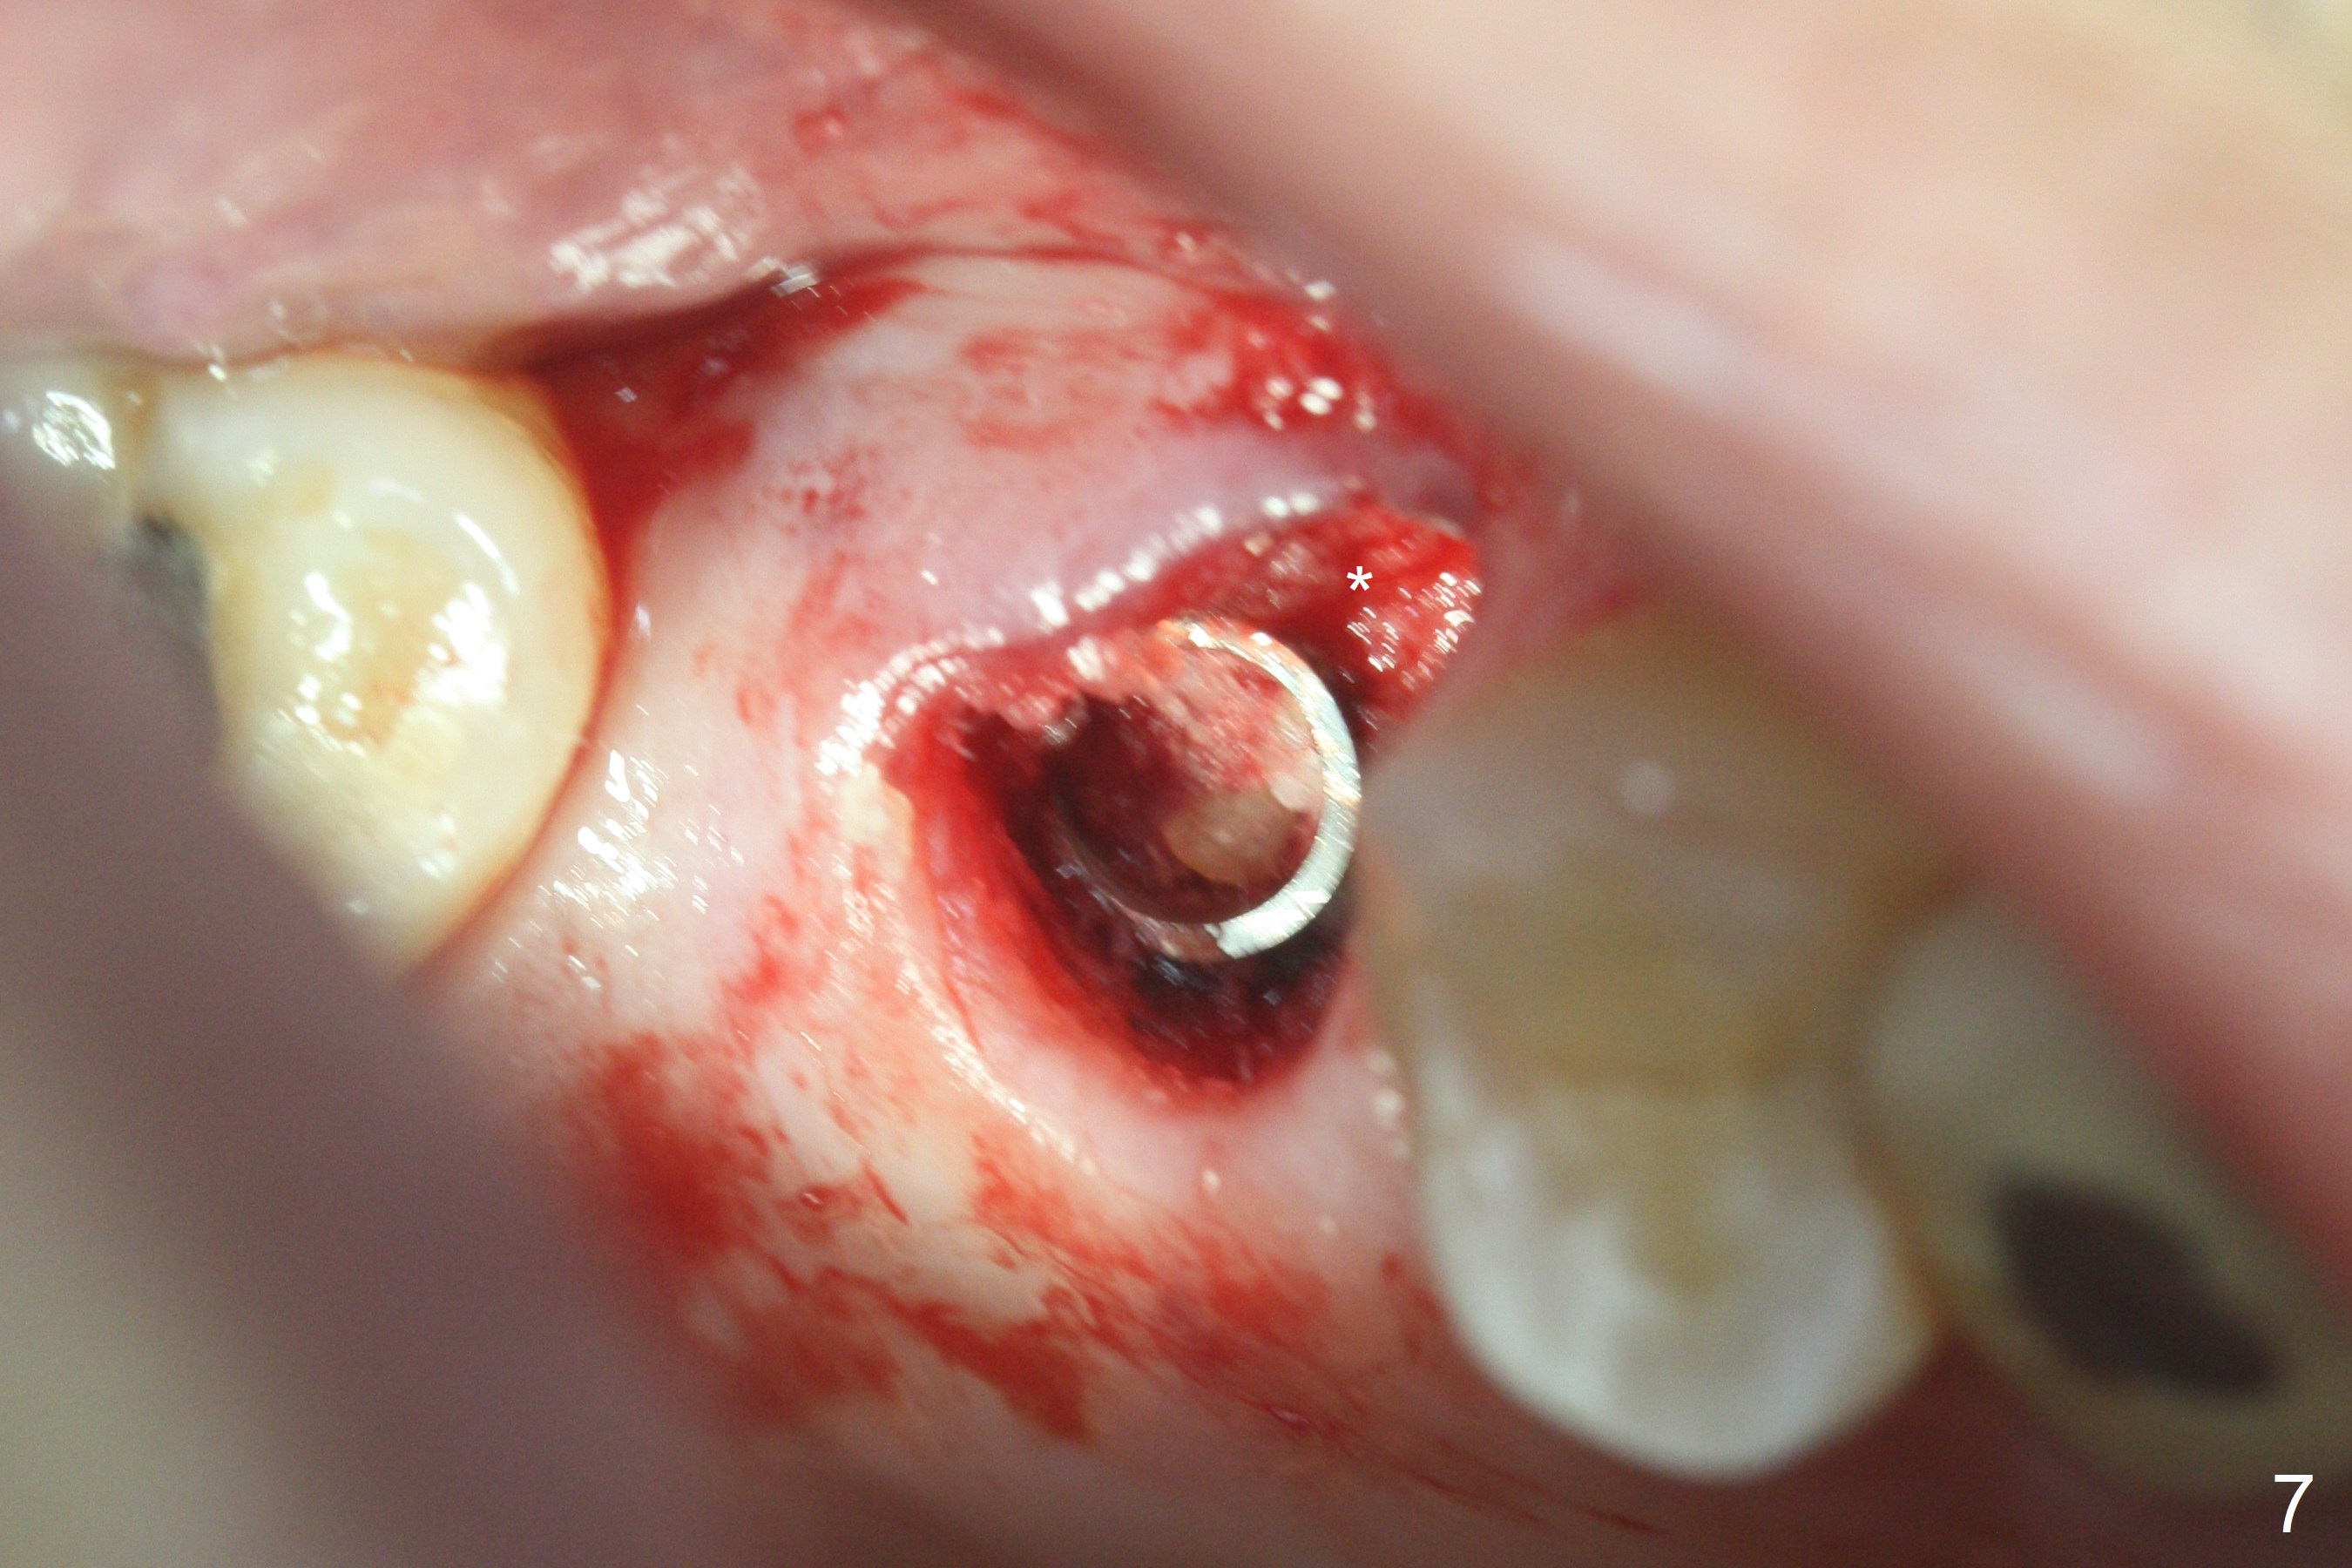

The palatal cusp of the affected 2nd premolar is apparently rotated distal (Fig.1). It is more obvious for the socket (Fig.2): the palatal (P) portion of the socket is more distal than the buccal (B) one. When the gauze is removed (Fig.3), Lindamann bur is used to remove the disto(D)palatal bone of the socket (data not shown), followed by starter drill in the DP wall obliquely (Fig.3'). Once the drill enters the bone for 1-2 mm, the bur is straightened and pushed slightly distal (Fig.3''). Fig.4 shows a parallel pin distal (overcorrect) to the original socket (Fig.4 red dashed line). Sequential osteotomy is conducted until 3.8x13 mm drill for 18 mm (Fig.5): note the 2 steps of the osteotomy (red lines). Since the apical portion of the osteotomy is larger than the drill, a larger implant than expected (5x16 mm) is placed. The implant ends up in the middle of the edentulous area (due to the stepped osteotomy; Fig.6-9; >60 Ncm). Vera allograft is placed (Fig.7-9 *) prior to and after placement of a 6.5x4(3) mm abutment (Fig.8-10). The remaining socket opening is sealed with a piece of Collagen plug (Fig.10 *). The socket is then closed by an immediate provisional (Fig.11 P). The abutment is retightened 2 months postop (Fig.12,13). The crown is cemented 4.5 months postop. Panoramic X-ray and CT are taken nearly 7 months post cementation (Fig.14,15) when the patient is ready for #30 implant guide preparation.